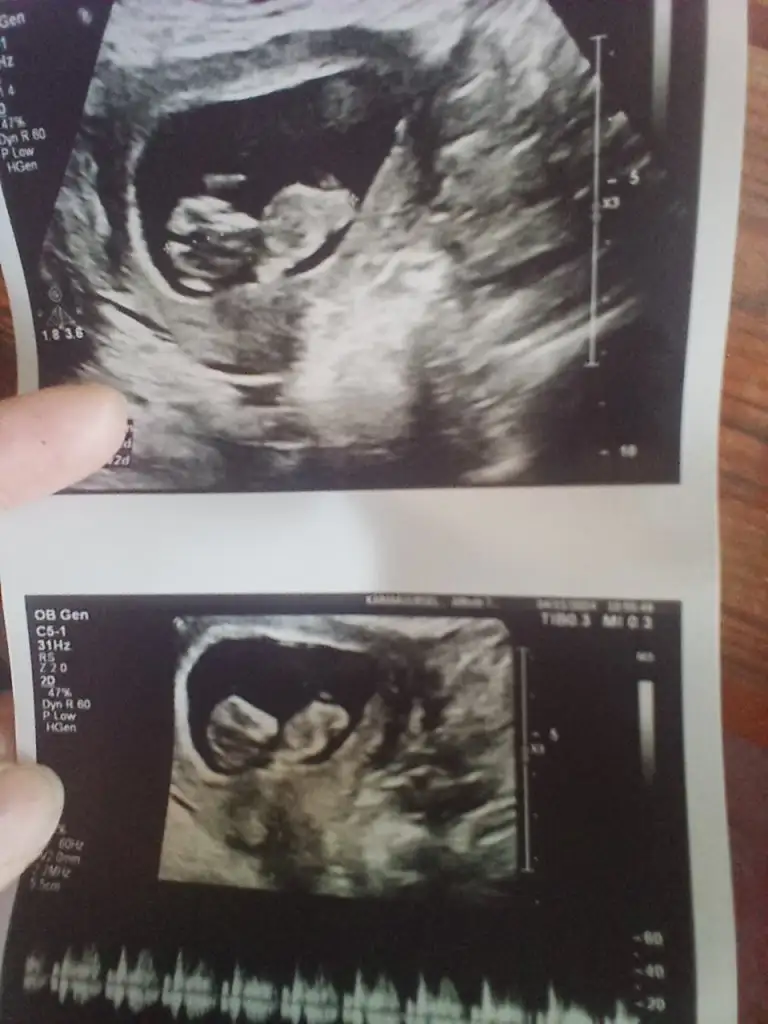

Bizde yorum alabilirmiyiz

• IMG-20241114-WA0046.webp

IMG-20241114-WA0046.webp

21,4 KB · Görüntüleme: 49

• IMG-20241104-WA0021.webp

IMG-20241104-WA0021.webp

28,7 KB · Görüntüleme: 39

• IMG-20241104-WA0019.webp

IMG-20241104-WA0019.webp

26,1 KB · Görüntüleme: 38